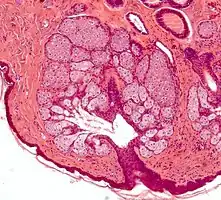

Les glandes sébacés ont une architecture acinaire (comme une grappe de raisin) et n'ont pas de lumières propre. Elles sont composés de sébocytes matures, dont la sécrétion est le résultat de leur mort par apoptose, ce qui revient à une sécrétion holocrine. Le remplacement des cellules est assuré par les cellules de la matrice reposant sur la membrane basale[5].L'annexe pilo-sébacée constituée du follicule pileux, des glandes sébacés et des muscles arrecteurs du poils, résulte d'une invagination épithéliale[4].

Annexe pilosébacée avec glandes sébacés s'abouchant à un follicule pileux.